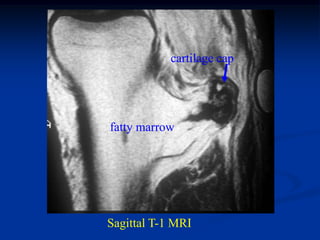

The solitaty osteochondroma or exostosis is one of the most

then stops at maturity. It is made up of a bony base with a pedunc-

ulated stock with fatty marrow extending up inside the stock that

has a cartilagenous cap giving it the appearance of a cauliflower.

cartilage cap

fatty marrow

Sagittal T-1 MRI